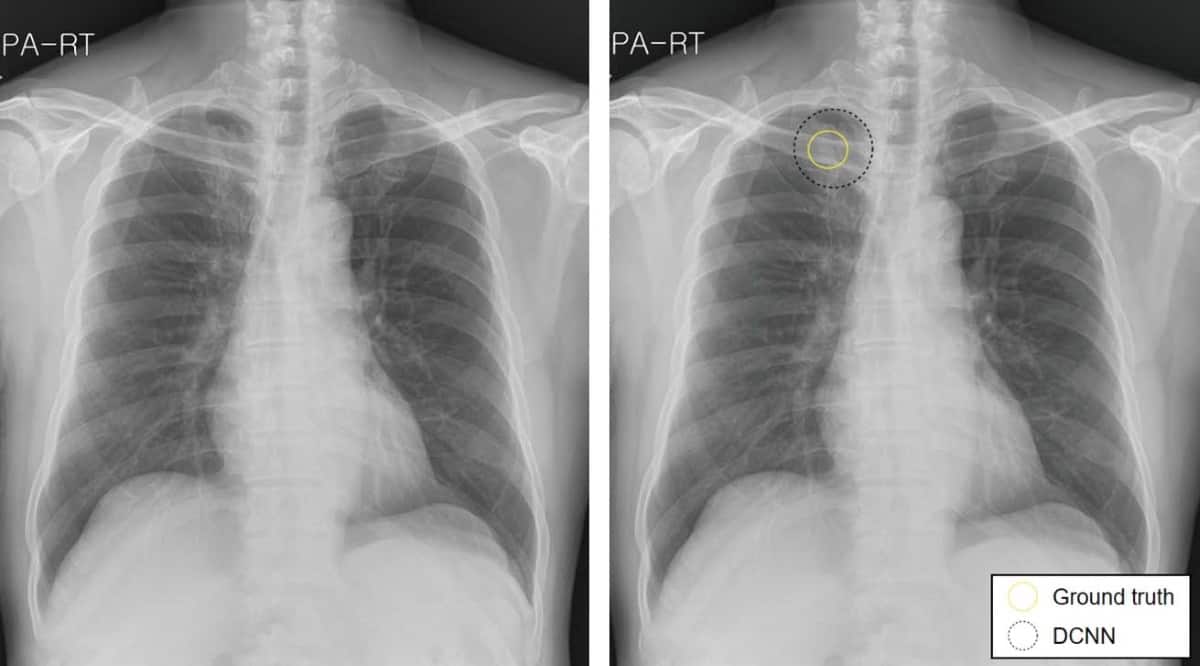

Lung Cancer Screening X Ray

Experience the clarity of Lung Cancer Screening X Ray with our curated collection of comprehensive galleries of images. featuring understated examples of photography, images, and pictures. designed to emphasize clarity and focus. Discover high-resolution Lung Cancer Screening X Ray images optimized for various applications. Suitable for various applications including web design, social media, personal projects, and digital content creation All Lung Cancer Screening X Ray images are available in high resolution with professional-grade quality, optimized for both digital and print applications, and include comprehensive metadata for easy organization and usage. Our Lung Cancer Screening X Ray gallery offers diverse visual resources to bring your ideas to life. Comprehensive tagging systems facilitate quick discovery of relevant Lung Cancer Screening X Ray content. Multiple resolution options ensure optimal performance across different platforms and applications. Time-saving browsing features help users locate ideal Lung Cancer Screening X Ray images quickly. The Lung Cancer Screening X Ray archive serves professionals, educators, and creatives across diverse industries. Instant download capabilities enable immediate access to chosen Lung Cancer Screening X Ray images. Whether for commercial projects or personal use, our Lung Cancer Screening X Ray collection delivers consistent excellence. Professional licensing options accommodate both commercial and educational usage requirements.